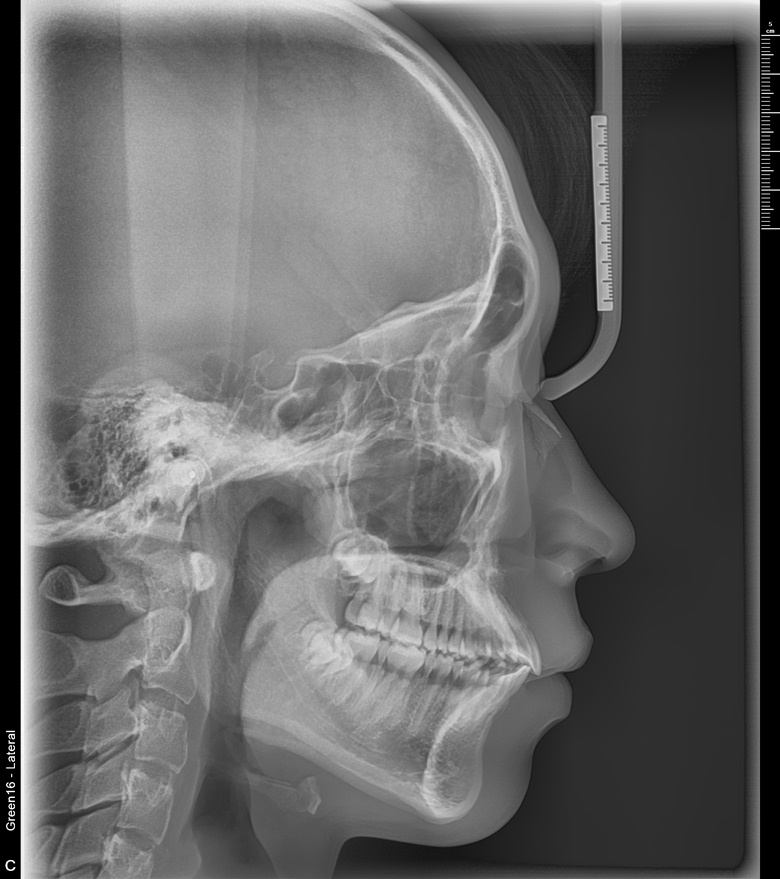

치료 전 사진입니다.